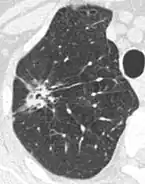

- Pleural retraction is far more common in cancers.[9] It is the pulling of visceral pleura towards the nodule.[9]

-

Nodule with pleural retraction.[9] -

In this case, pleural retraction is seen as a triangular fat component.[9]